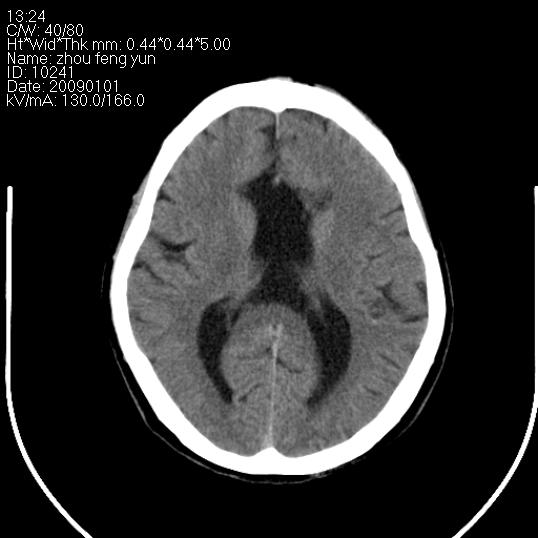

以下是引用hhcckk在2009-1-1 16:39:00的发言:[br]胼胝体嘴、膝部及部分体部发育不全,为囊状影替代,两侧侧脑室分离,脑室后角扩张[br][br]诊断:胼胝体发育不良[br][br]胼胝体发育不良(dysgenesis of the corpus callosum)是最常见的颅脑畸形,是胚胎期背部中线结构发育不良的一种形式。主要包括胼胝体缺如和部分缺如。胼胝体发育不良还可合并其他畸形,如胼胝体脂肪瘤、蛛网膜囊肿、脑膨出、chiari畸形、灰质异位症、脑回畸形等。[br][br]ct诊断要点:[br]1. ct横断扫描可见两侧侧脑室明显分离,脑室后角扩张,形成典型的蝙蝠翼状侧脑室外形。[br]2. 第三脑室扩大并向上插入两侧脑室体部之间,严重者第三脑室可上移到两侧大脑半球纵裂的顶部。在ct冠状扫描位显示更清。[br]4. 胼胝体畸形常伴有脂肪瘤,可测到其特征性脂肪密度。部分脂肪瘤的边缘可出现线样钙化[br]